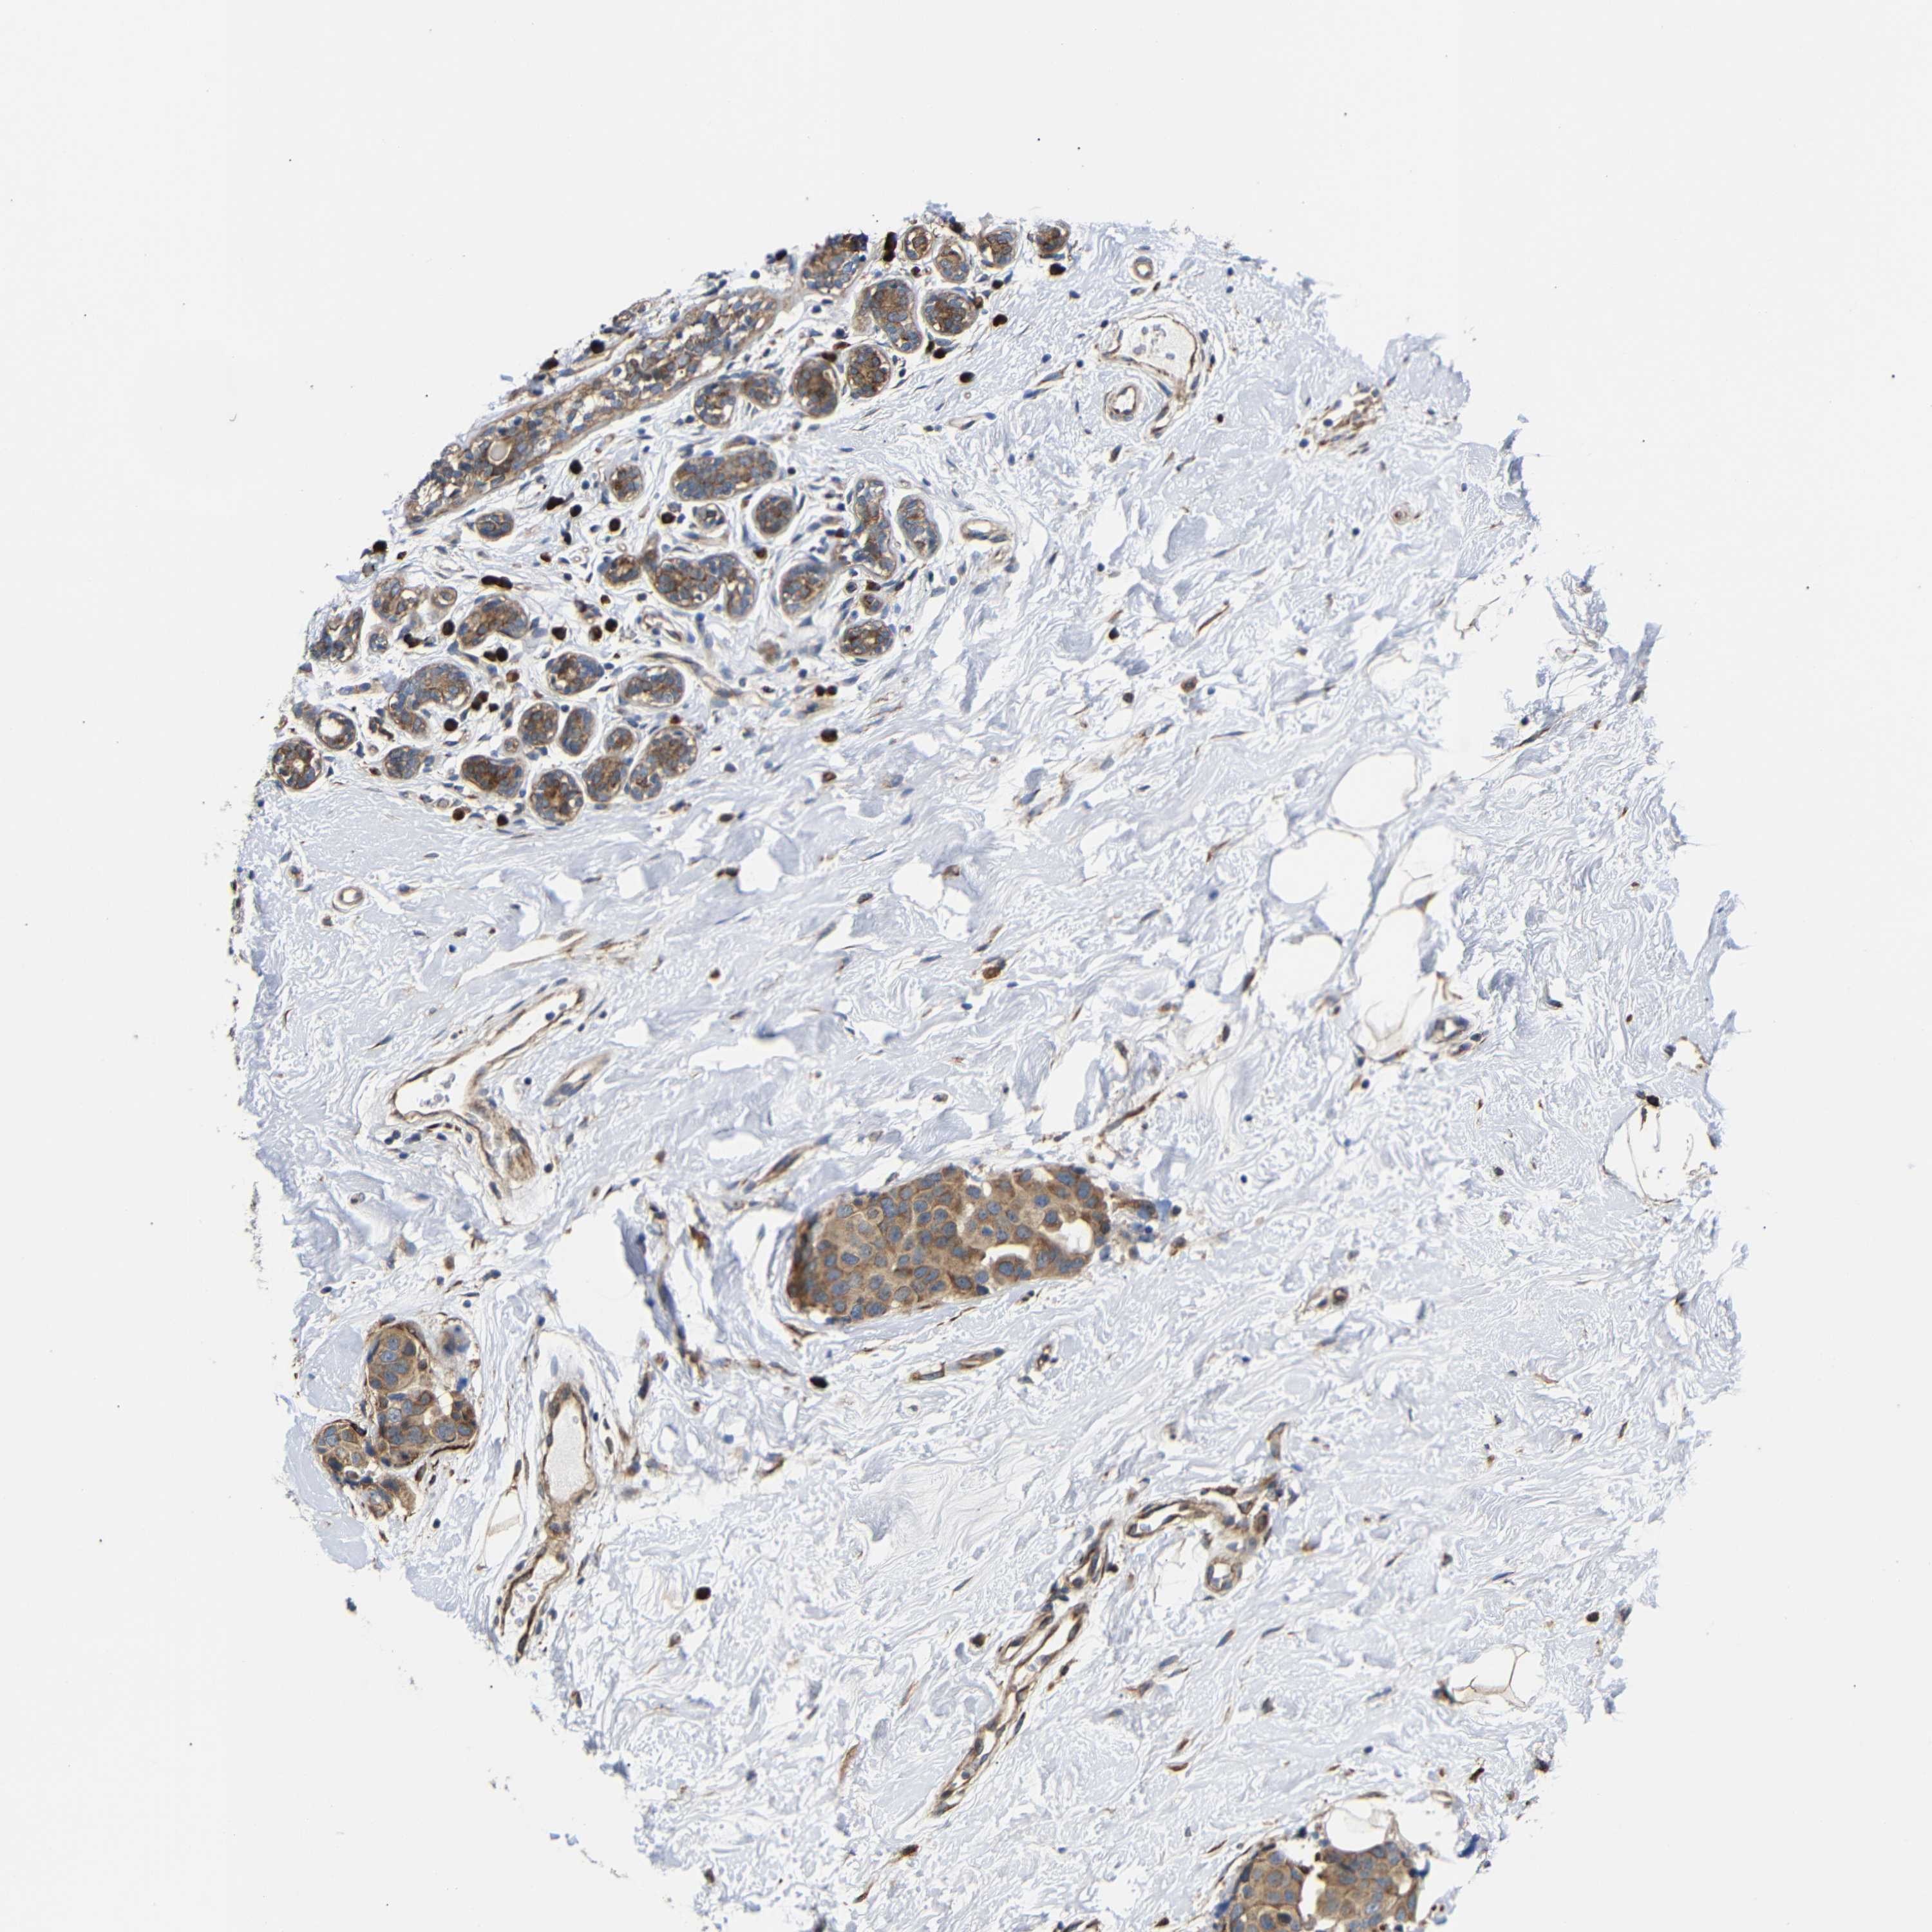

BRCA TCGA BRCA VALIDATION PROTEIN EXPRESSION